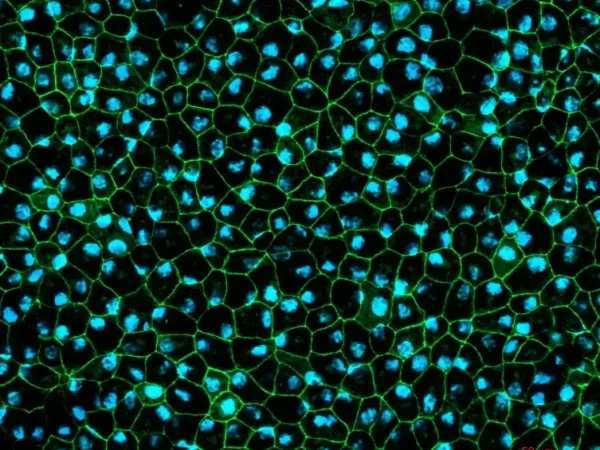

RPE cells displaying cobblestone morphology. Cells were immunolabeled with tight-junction ZO-1 marker (shown in green) and co-stained with nuclei marker, Hoechst (shown in blue). Image Credit: Newcells Biotech

Human iPSCs forming a two-dimensional layer generate in vitro retinal pigment epithelial cells, which are pigmented and display typical cobblestone morphology.

The in vitro model closely recapitulates crucial functions found in vivo, including tight barrier formation and photoreceptor outer segment phagocytosis.